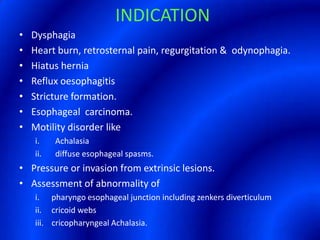

This document provides information about a barium swallow procedure. It begins with an introduction and overview of the embryology and anatomy of the pharynx and esophagus. It then describes the procedure itself, including preparation, technique, views obtained, and indications. Specific conditions that may be examined include pharyngeal and esophageal webs, foreign body impaction, scleroderma, dysphagia, mediastinal masses, and carcinoma. Diagrams are provided to illustrate normal anatomy and various pathological findings.